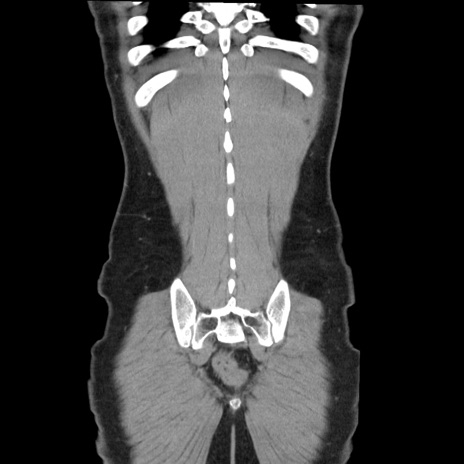

症例36(冠状断像)

【症例】20歳代 男性

【主訴】心窩部痛

【現病歴】今朝より上腹部痛あり。一旦軽快していたが再度出現したため救急要請。昨日夕に白身の魚を含む刺身を食べた。

【身体所見】BP 136/89mmHg、HR 74/min、BT 37.0℃、腹部:膨満、軟、心窩部に圧痛あり。反跳痛なし、筋性防御なし、腸雑音やや亢進あり。

【データ】WBC 17700、CRP 0.48